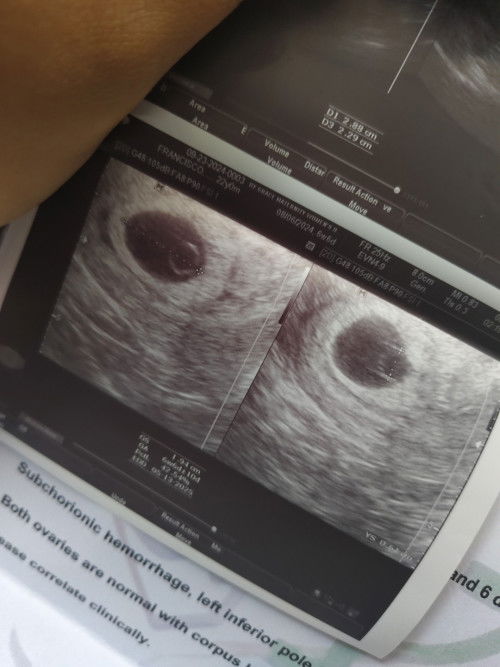

Supposed to be 6w and 6d ako yesterday which is tumama naman sa sukat but wala pang makita na embryo, pinapainom na kase agad ako ng ob pagpalambot ng cervix pero di ako convince na Blighted Ovum na to. hindi ba dapat magantay muna ako until kahit mga 8 weeks? Ang plano ko po is magpatvs ulit sa 9weeks ko, kase may progress hindi naman sya huminto pa sa progress and also may subchorionic hemorrhage ako but hindi ako nagsspotting, since ayoko na nga bumalik sa ob na yon dahil ang binibigay nya is pampalambot na ng cervix ano suggestions nyo na gawin while waiting? and also anong thoughts nyo sa blighted ovum na ba talaga ayan ultasound